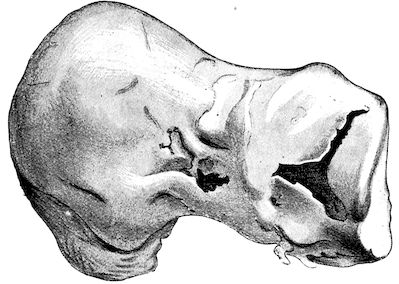

Fig. 1.—Rachitis in a young goat.

Fig. 1.—Rachitis in a young goat.